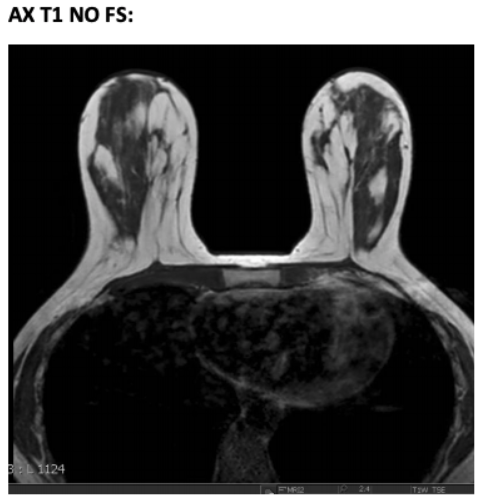

Breast MRI - Siemens Healthineers USA。Breast Imaging:MRIシステム | 富士フイルム [日本]。MR Bilateral Breasts WWO Protocol | OHSU。乳房MRIの最新技術と応用に関する詳細な情報を提供する専門書。- タイトル: Breast MRI: State of the Art and Future Directions- 巻号: Volume 5- 編集者: Kaya P. Pincus, Ritesh Mann, Savannah Partridge- 出版社: Academic Press- 内容: 乳房MRIの最新技術と応用に関する情報- キーフィーチャー: 乳房MRIの技術、解釈、最新の研究成果に関する情報ご覧いただきありがとうございます。。MRI-Women's Healthに対するトータルコンセプト“Elite Breast”-技術。病気がみえる 見える 15冊セット売りお店の情報